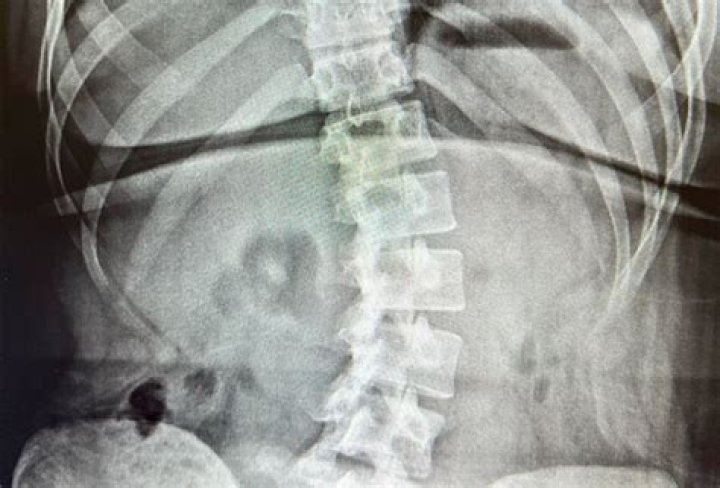

Yes, chiropractors will often utilize x-rays to better understand a patient’s health or problem. Chiropractors are trained to recognize the areas of the spine that may cause problems. X-rays allow them to see these problem areas, allowing them to better diagnose what is causing a patient’s pain or discomfort.

An x-ray could reveal an underlying condition that is causing a patient’s problem. For example, if someone has severe neck pain and the chiropractor see’s an abnormal curve in their spine, they will most likely order an x-ray to determine what is causing the pain.

Spinal problems such as arthritis and osteoporosis can also be diagnosed with x-rays. Since these conditions affect the spine and bones, an x-ray will reveal any abnormalities that may be present in a patient’s back or neck.